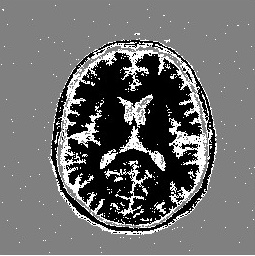

We illustrate the performance of Algorithm 1 when applied to the well-known MRI and cameraman images. Figure 1 shows results of completion for the MRI image determined by Algorithm 1, the CNC algorithm [17], and the ATCG-TV algorithm [4] for 90%90\% missing data (SR=0.1=0.1). Table 1 reports PSNR-values, CPU-times (in seconds), and the number of iterations (Iter) required by each algorithm to satisfy the stopping criteria. The stopping criteria for the ATCG-TV and CNC algorithms were the default choices provided in [4] and [17], respectively.

Refer to caption Refer to caption Refer to caption Refer to caption Refer to caption

Original Observed CNC ATCG-TV LR-CNC

Fig. 1: Recovered MRI images by the CNC, ATCG-TV, and LR-CNC algorithms for SR=0.1=0.1.

MRI 0.1 21.22 20.22 730 18.44 8.20 968 21.36 4.54 174

0.2 23.14 5.68 355 21.96 7.13 782 23.37 2.69 98

0.3 25.01 4.00 262 24.37 8.56 889 25.32 1.65 60

Cameraman 0.1 21.34 11.53 757 19.31 6.58 770 21.52 5.09 184

0.2 23.11 5.52 361 22.11 7.31 785 23.27 2.64 91

0.3 24.33 3.35 220 24.08 6.90 755 24.70 1.66 58

Table 1: PSNR-values of the restored images, CPU-times, and number of iterations by the CNC, ATCG-TV, LR-CNC methods for various values of SR.

Figure 1 and Table 1 show that for small SR-values, the LR-CNC algorithm outperforms the ATCG-TV algorithm. However, for larger SR-values, the difference in performance between the two algorithms is less significant. The LR-CNC algorithm demonstrates a clear advantage in terms of CPU time and the number of iterations required in comparison with both the CNC and ATCG-TV algorithms. Figure 2 displays the graphs of the logarithm of the mean square error versus the number of iterations for the LR-CNC, CNC, and ATCG-TV algorithms, as well as the values of